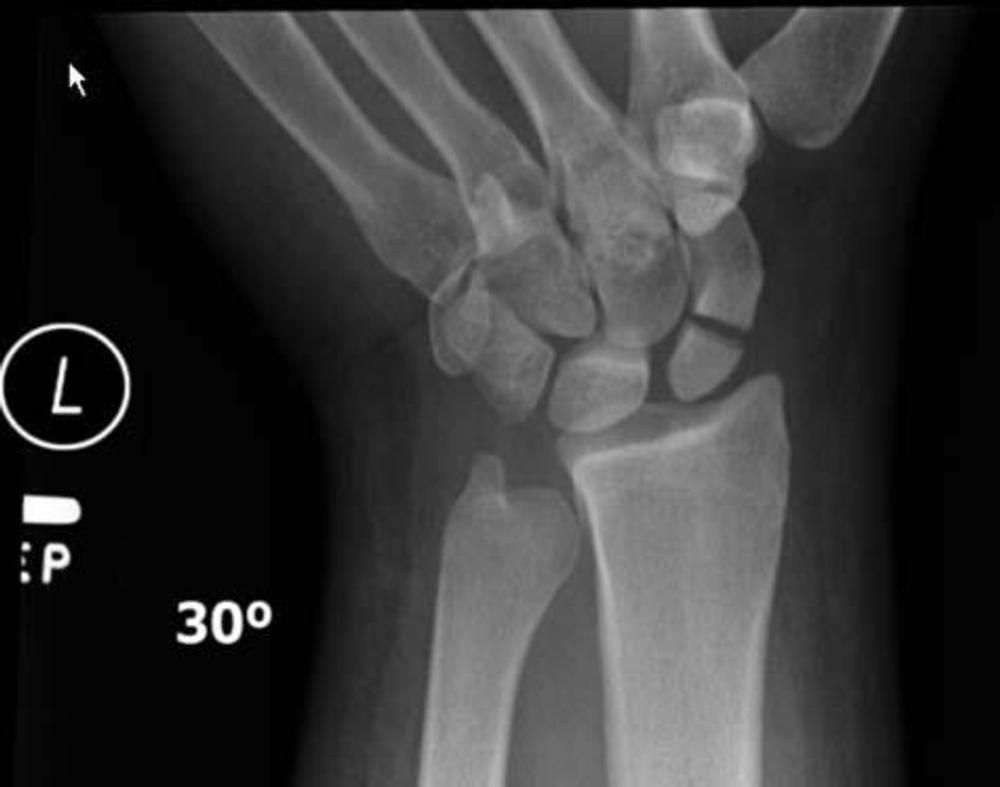

Nineteen of the 36 patients were found to have a radiographically apparent injury. The most common injuries involved the upper extremities, particularly the wrist. There were six cases of distal radial fractures, or fracture of the forearm bone close to the wrist, making it the most common injury in the study group. Soft tissue injuries of the head, face, wrist and ankle, were present in five cases.

Figure 3. X-ray image of a fracture of the scaphoid bone in the left wrist.